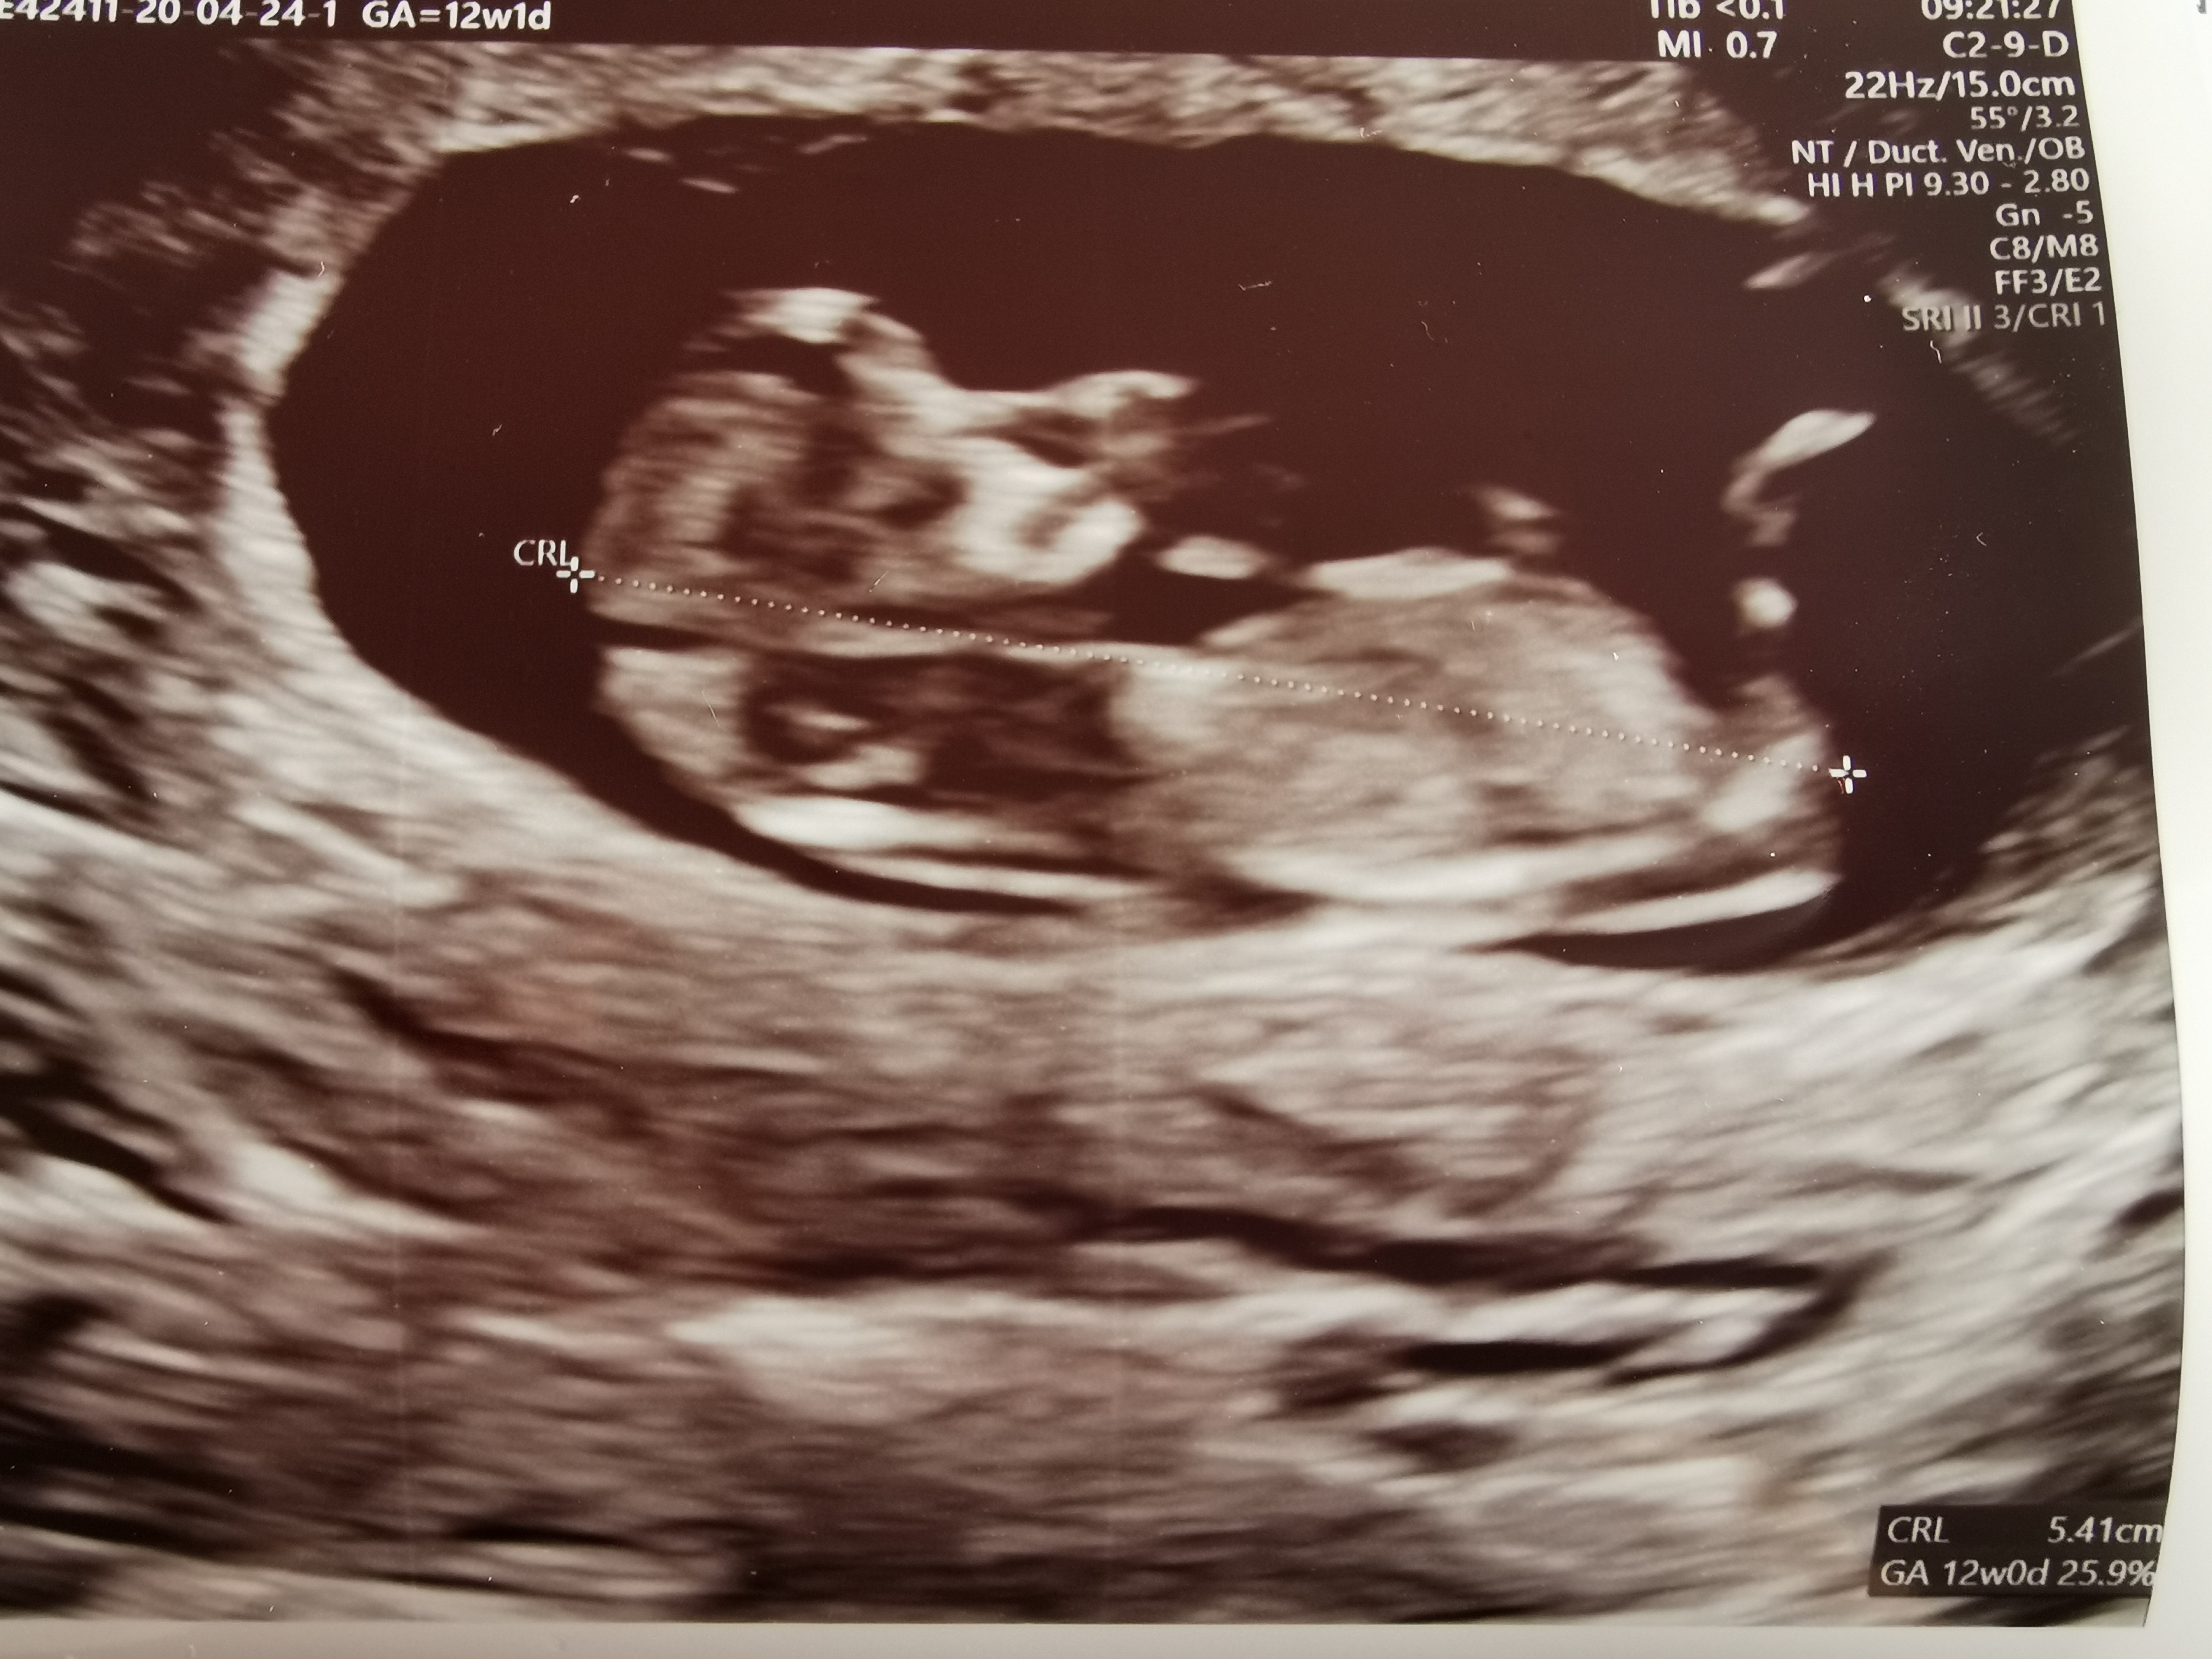

Z dobrych info to w tym tygodniu przyszły wyniki SANCO, miałam tez usg prenatalne i wszytsko jest ok. Będzie chłopak

, który ka teraz 6,24 cm